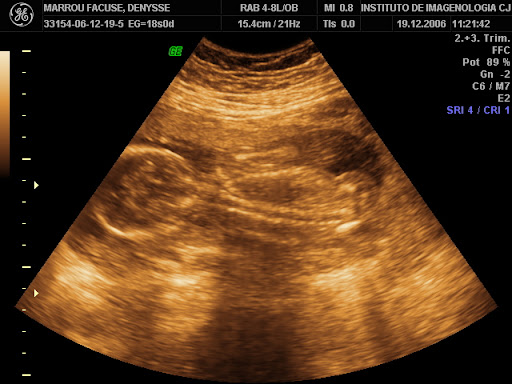

Dios nos regalo un retoñito. En este Blog iremos subiendo todo el proceso de su crecimiento.

En esta foto vemos a nuestro bb de 18 semanas.